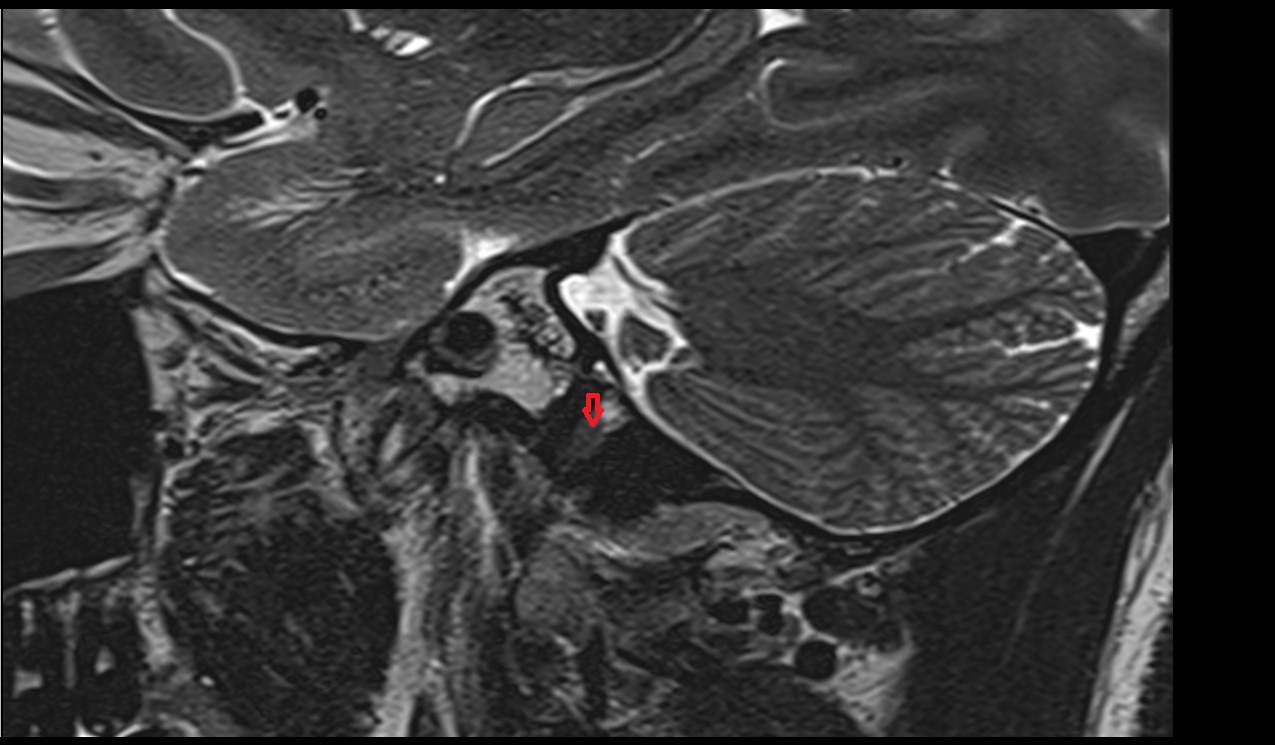

- Temporomandibular joint

- Mandibular condyle

- Mandibular fossa

- Articular disc of temporomandibular joint

- Articular eminence